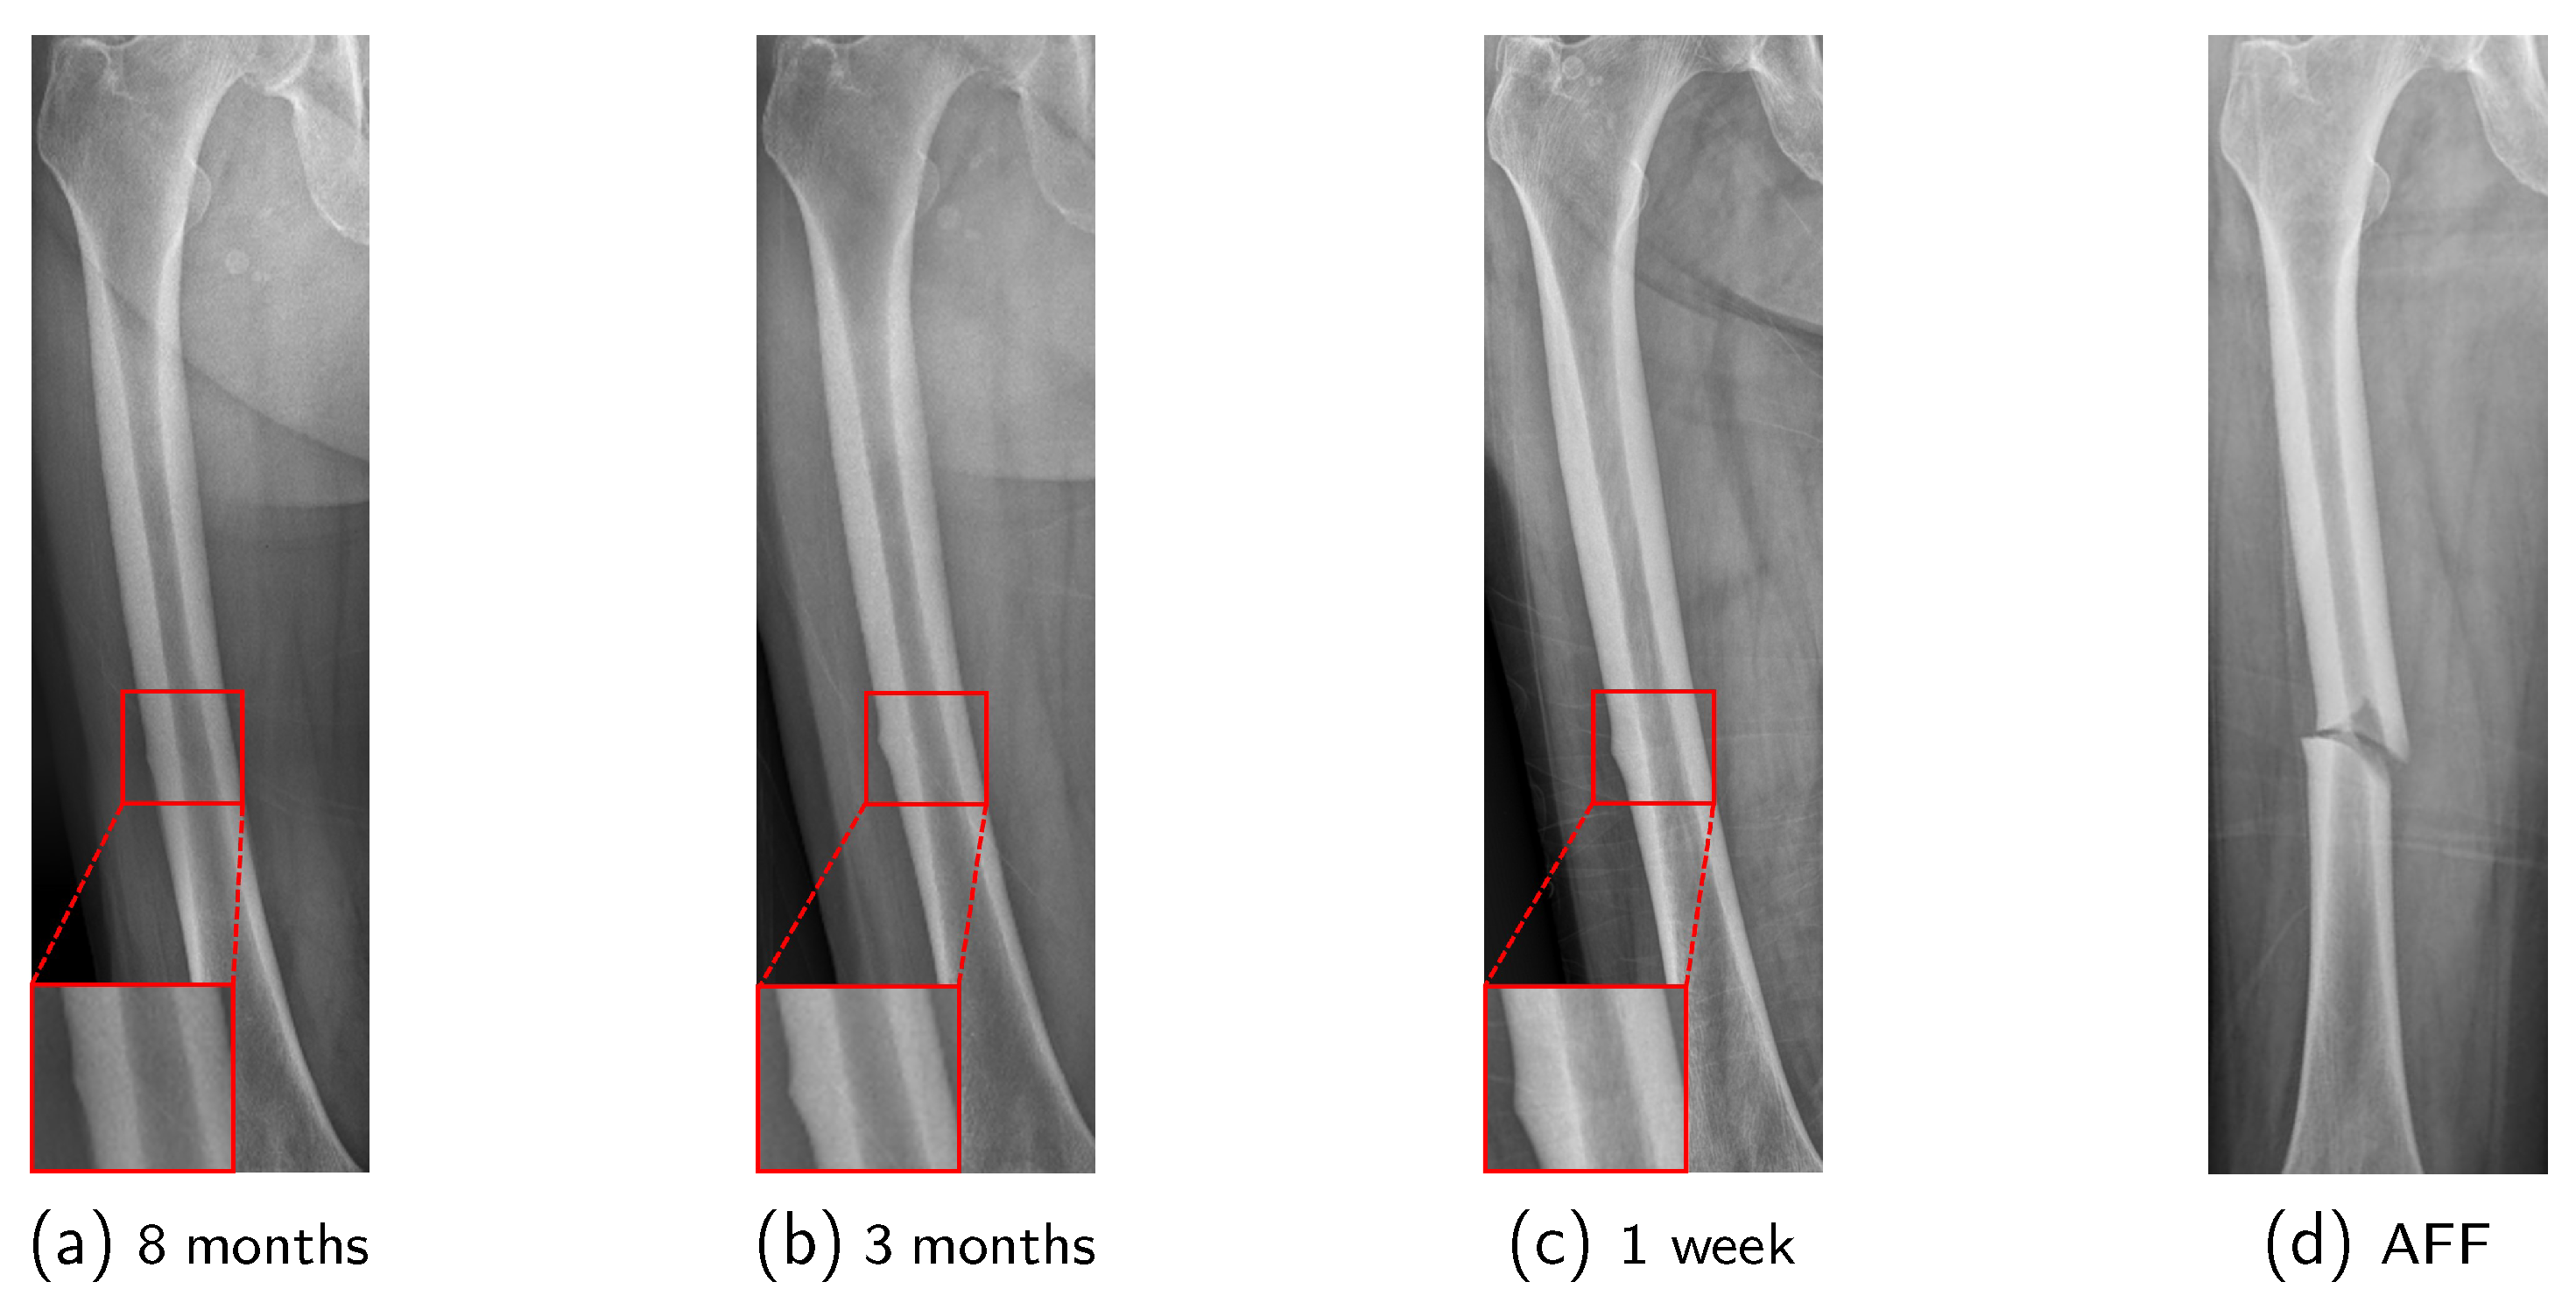

In the early stages preceding the occurrence of AFF, cortical buckling will develop in the lateral cortex of the femur due to repeated cycles of microfracture and healing [12]. This condition is termed Incomplete Atypical Femoral Fracture (IAFF). IAFF exhibits various characteristics and is classified based on its location as shown in Figure 1: Diaphyseal IAFF (D-IAFF), which occurs in the femoral shaft, and Subtrochanteric IAFF (S-IAFF), which occurs in the subtrochanteric region [13]. Although IAFF is a crucial precursor to AFF, it is often asymptomatic or presents with vague features, making detection difficult and often resulting in delayed diagnosis. As a precursor to AFF, the progression process from IAFF to AFF is illustrated in Figure 2. IAFF is typically diagnosed through bone scans [14] or Magnetic Resonance Imaging (MRI) [15]. However, these diagnostic methods have notable drawbacks, including high costs and time consumption. Furthermore, there remains the risk of misdiagnosis [14], which can lead to either unnecessary or delayed interventions, ultimately culminating in a complete fracture.